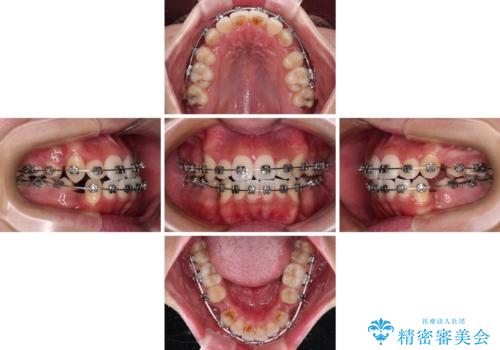

- メタルブラケット

- 2年4ヶ月

- 10-30回